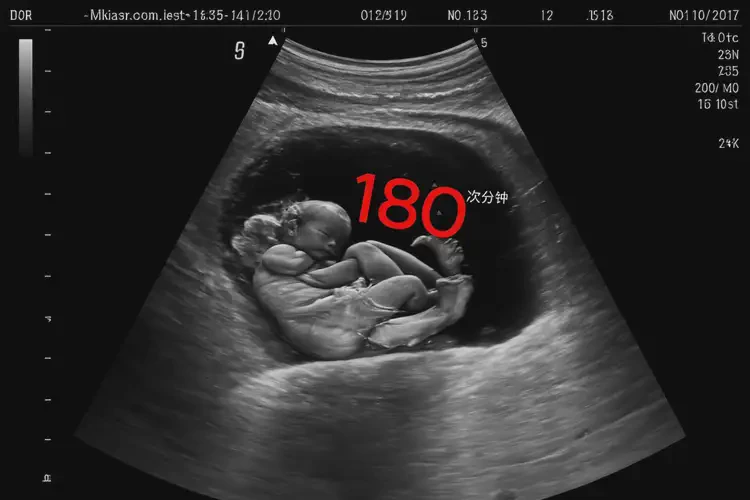

孕10周1天胎心率180宝宝还能要吗

胎心率180次/分钟在孕10周1天属于正常范围,宝宝可以要。

孕10周1天时,胎儿的胎心率在170-190次/分钟之间都被认为是正常的。胎心率会随着孕周的增加而逐渐下降,到孕晚期会稳定在120-160次/分钟。180次/分钟的胎心率在这个时期是可以接受的,并不意味着宝宝有问题。

孕10周1天胎心率180宝宝还能要吗(图1)